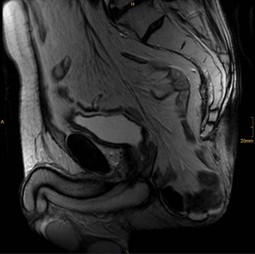

Bei einem 66-jährigen Patienten kam es 2 Jahre nach abdominoperinealer Rektumamputation und adjuvanter Chemotherapie bei einem T2N0M0-Adenokarzinom des Rektums zu einer perinealen Hernie. Die Diagnose wurde mittels Magnetresonanztomographie bestätig und die operative Versorgung erfolgte offen chirurgisch durch einen perinealen Zugang mittels Implantation eines Kunststoffnetzes.

A 66-year-old man presented with a painful perineal tumor 2 years after abdominoperineal excision for rectal adenocarcinoma. Perineal hernia was confirmed by magnetic resonance imaging, and the patient underwent open mesh repair through a perineal approach.